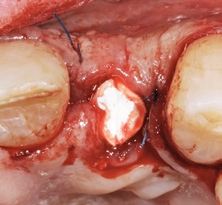

Extraoral wurde das explantierte Implantat auf Vollständigkeit geprüft, indem die beiden Teile passgenau aufeinandergelegt wurden (Abb. 6). Nach sorgfältiger Kürettage, intensiver Spülung und Dekontamination der Defektstelle wurde das prothetisch orientierte Implantatlager mit den entsprechenden Formbohrern für das CERALOG Hexalobe Implantat (12 mm L, 4 mm Ø) über den bestehenden Implantatfundus hinaus apikal aufbereitet (Abb. 7). So konnte eine ausreichende Primärstabilität des Implantats erzielt werden. Um einen ausreichenden Knochen-Implantat-Kontakt zu erreichen, musste der Stollen mit einem Gemisch aus autologen Knochenspänen und Bio-Oss Collagen (Geistlich) vor der Insertion augmentiert werden (Abb. 8) [15]. Das Implantat wurde mit dem Eindrehinstrument aus dem Blister genommen und manuell in das Knochenfach inseriert. Das Implantat erreichte eine Primärstabilität von 20 Ncm. Das Design der Innenkonfiguration trägt dem Material Zirkoniumdioxid Rechnung. Die optimierte Hexalobe-Verbindung erlaubt beispielsweise eine höhere Kraftübertragung als eine Sechskantinnenverbindung. Beim Einbringen wird die Kraft radial in das Implantat eingeleitet und Spannungsspitzen werden vermieden.

Wegen der niedrigen Wärmeleitfähigkeit des Zirkoniumdioxids werden die CERALOG Implantate mit maximal 15 U/min eingedreht. Bei zu schnellem Eindrehen kann es zu einer Temperaturerhöhung von bis zu 20 Grad kommen mit negativen Folgen für das periimplantäre Hartgewebe. Daher wurde das Implantat mit einer handgeführten Ratsche unter ständiger Kontrolle des Drehmoments (bis zu max. 35 Ncm) inseriert (Abb. 9). Die Implantatschulter wurde 1 mm suprakrestal platziert, sodass die prothetische Plattform zirka 0,5 mm unter dem Weichgewebeniveau zu liegen kommt. Die CERALOG Implantate sind mit einer dualen Oberflächentextur versehen. Sie vereint zwei definierte Rauigkeiten. So ist der enossale Bereich mit einer Mikrorauigkeit von 1,6 ?m für die gezielte Anlagerung der Knochenzellen versehen. Für eine gute Weichgewebeadaption ist der Halsbereich des Zirkoniumdioxidimplantats mit einem Ra-Wert von 0,5 ?m versehen. Die Implantatpositionierung entspricht dem Übergangsbereich von glatter zu rauer Oberflächentextur auf Knochenniveau [16].

Mit der PEEK-Abdeckkappe, die über einen Klickmechanismus in die Innenkonfiguration des Implantats gesteckt wird, wurde das Implantat verschlossen. Die Abbildung 10 zeigt die optimale prothetisch orientierte Platzierung des Implantats für die Rekonstruktion mit einer direkt verschraubten Hybridabutmentkrone. Von okklusal ist das ausgeprägte bukkale Knochendefizit deutlich zu sehen. Mit einem Gemisch aus autologen Knochenspänen, die während des Bohrvorgangs implantatnah gewonnen worden waren, und Bio-Oss Collagen (Geistlich) wurde der Defekt aufgebaut. Aufgrund ihrer osteogenetischen, -induktiven und -konduktiven Eigenschaften ist der Einsatz von autologen Knochenspänen in der GBR in unserer Praxis Standard. Eine resorbierbare Membran mit verlängerter Barrierefunktion (Memlok BioHorizons) wurde nach Ablösung des Periosts, dem biologischen Konzept folgend, zur Abdeckung des volumengebenden Augmentats in direktem Kontakt zur angrenzenden Knochenoberfläche eingebracht (Abb. 11) [17, 18]. Resorbierbare Kollagenmembranen zeichnen sich dadurch aus, dass der Heilungsprozess der Weichgewebe auch bei Exposition der Membran weiter voranschreitet. Ein Kollagenkegel (Parasorb, Resorba) wurde zum Verschluss des gingivalen Defektbereichs eingesetzt, bevor das Weichgewebe spannungsfrei vernäht (Prolene 5-0, Ethicon) und ein postoperatives Röntgenkontrollbild gemacht wurde (Abb. 12–14). Die temporäre Versorgung erfolgte durch eine Kunststoff-Klebebrücke.